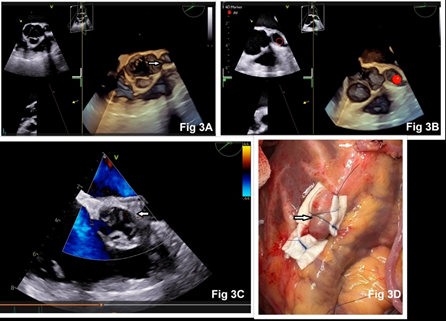

A 57-year-old female presented to our hospital with hypertension and unstable angina in July 2025. She has undergone coronary angiography and a failed attempt at PCI in the previous hospital. Her past records were unavailable. She denied any history of chest trauma, infection, pericarditis, or previous myocardial infection. On examination, she had a pulse of 65 beats/minute, a blood pressure of 160/90 mmHg, and a respiratory rate of 20 breaths/minute. Physical examination and laboratory tests were normal. Electrocardiography showed poor progression of ‘r’ waves in leads I and aVL, and T-wave inversion in the precordial leads (V1-V5, Fig 1). Transthoracic echocardiography showed akinetic mid anterior septum, mid anterior wall, and apex with an ejection fraction of 35%. Coronary angiography revealed a saccular aneurysm of the LMCA, measuring 20 mm x 26 mm. There was 90% stenosis of the LAD, 95% stenosis of the left circumflex artery, and a normal right coronary artery (Fig 2). In view of the LMCA aneurysm and double vessel CAD, the surgical option was considered. Intraoperative transesophageal echocardiography confirmed the presence of LMCA aneurysm (Fig 3A, 3B). Using cardiopulmonary bypass, the ascending aorta was opened and the LMCA aneurysm was oversewn and closed from its origin in the aortic sinus by 3-0 polypropylene pledgeted suture (Fig 3C). The proximal segment of the LAD was also aneurysmal, and it was ligated proximally and distally using pledgeted polypropylene suture (Fig 3D). The LAD and obtuse marginal artery were bypassed using vein grafts as conduits. The patients had an uneventful hospitalization and was discharged on the sixth postoperative day on dual antiplatelet therapy.

Figure 3: Intraoperative 3-D transesophageal echocardiography showing aneurysmal LMCA arising from the left aortic sinus (arrow and red circle 3A, 3B). Closed communication between aortic sinus and LMCA after its ligation (3C). Surgical photograph showing ligation of aneurysmal LAD artery (black arrow) and vein graft anastomosed to distal LAD (white arrow).